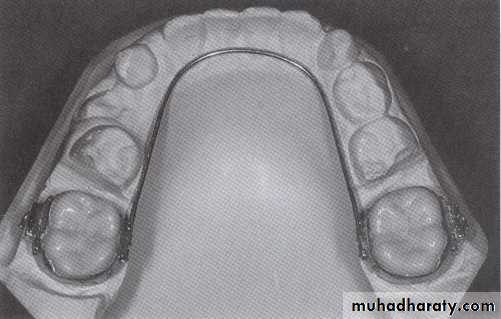

A- Reduction in size of primary canine.B- Expansion of arch, by tipping the molars distally and incisors slightly foreword while widening the arch in premolar area.

C- Extraction of primary canine but this create a possibility that permanent incisor will tip lingually reducing arch length, a conservative approach to place a lingual arch in canine extraction.